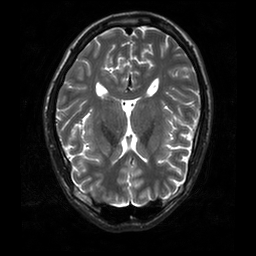

Reconstructing magnetic resonance (MR) images from undersampled data is a challenging problem due to various artifacts introduced by the under-sampling operation. Recent deep learning-based methods for MR image reconstruction usually leverage a generic auto-encoder architecture which captures low-level features at the initial layers and high?level features at the deeper layers. Such networks focus much on global features which may not be optimal to reconstruct the fully-sampled image. In this paper, we propose an Over-and-Under Complete Convolu?tional Recurrent Neural Network (OUCR), which consists of an overcomplete and an undercomplete Convolutional Recurrent Neural Network(CRNN). The overcomplete branch gives special attention in learning local structures by restraining the receptive field of the network. Combining it with the undercomplete branch leads to a network which focuses more on low-level features without losing out on the global structures. Extensive experiments on two datasets demonstrate that the proposed method achieves significant improvements over the compressed sensing and popular deep learning-based methods with less number of trainable parameters. Our code is available at https://github.com/guopengf/OUCR.